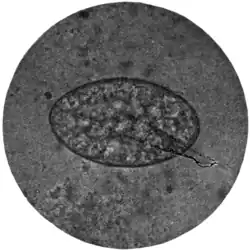

Fig. 194.—Ovum of Fasciolopsis buski, x 250. (Photograph by Dr. J. Bell.)